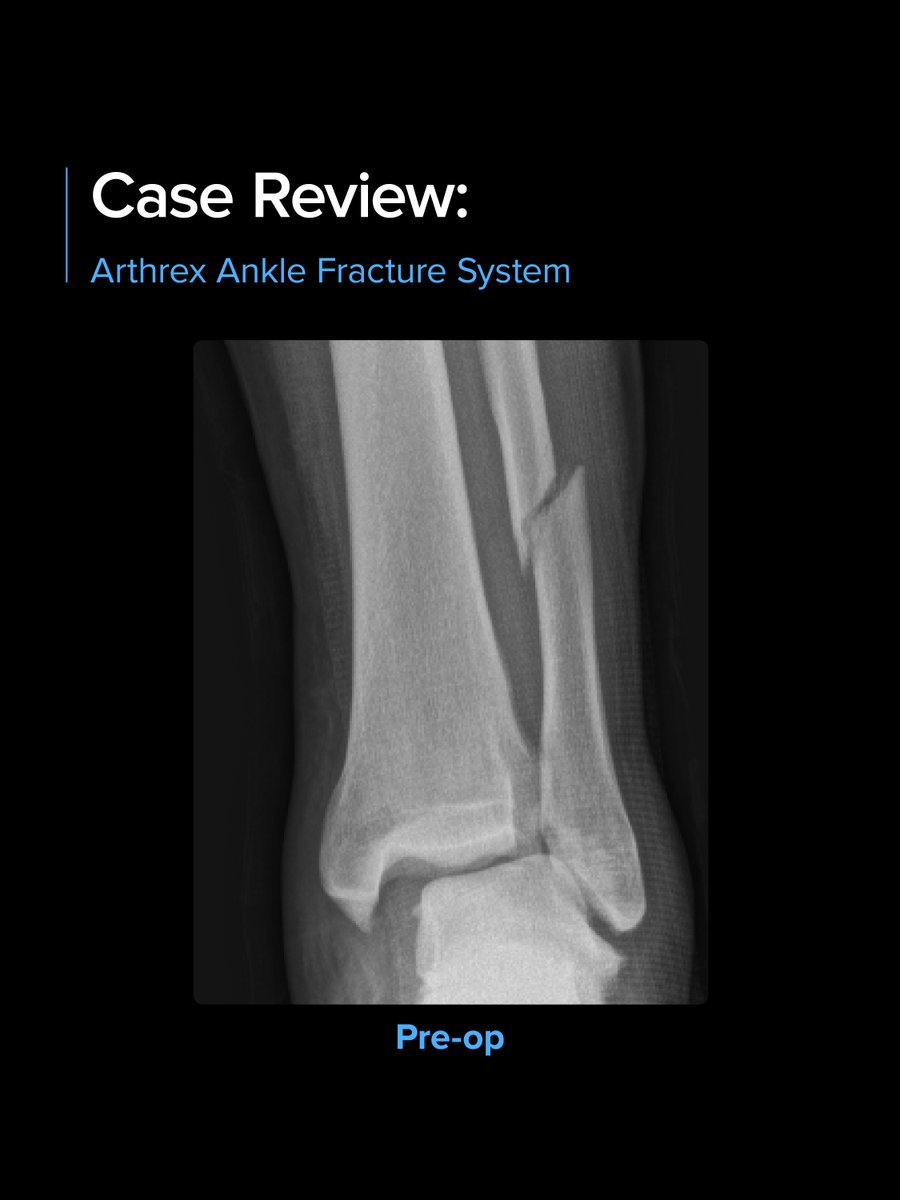

Case Review: Ankle Fracture, InternalBrace™ Ligament Augmentation Repair, and Syndesmosis TightRope® XP Implant System A 22-year-old male sustained an isolated rotation ankle injury while playing football. The mechanism of injury was a direct lateral force by another player, followed by external rotation. X-rays showed a proximal Weber C oblique fibular fracture with widening of the tibiotalar clear space and medial clear space. Surgical Technique Establish standard anterior medial and anterolateral portals. Introduce the NanoScope™ through the anteromedial portal. Debride the acute synovitis and hemorrhagic plug as well as the syndesmosis. Direct lateral approach — Apply a fibular ORIF using a long 1⁄3 tubular plate in a posterolateral fashion. Clamp the plate to the bone and use as a reduction tool, which is useful with more proximal short oblique fibular fractures. Inspect and debride the syndesmosis and reduce manually with temporary K-wire fixation. Debridement is critical to ensure no soft tissue or bone will impede the fibula from falling back into the tibial incisura. Multiligament stabilization of the syndesmosis 1. Secure the InternalBrace ligament augmentation repair into the distal fibula in an anterior-to-posterior fashion using a 3.5 mm SwiveLock® anchor. 2. Prep the anterolateral tibia for the 4.75 mm SwiveLock anchor using a 3.4 mm drill and 4.75 mm tap. Leave the tap in the tibia until the TightRope implants are placed to avoid drilling into the anchor. 3. Insert 2 Syndesmosis TightRope XP implants through the end of the ⅓ tubular plate. 4. Insert the SutureTape into the anterolateral tibia using a 4.75 mm SwiveLock anchor to close down the anterior syndesmosis. Courtesy of Spencer Monaco, DPM Learn more: arthrex.info/4bAa10C